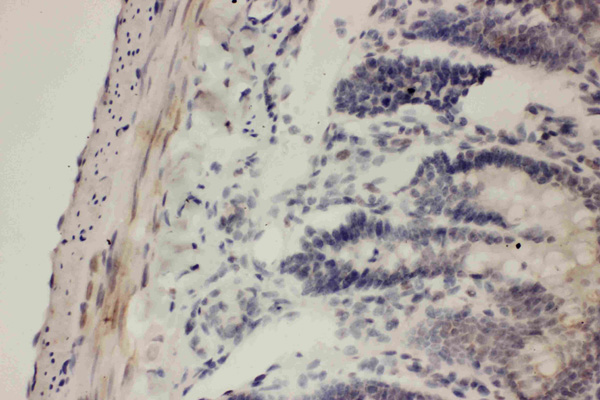

IHC (Immunohistochemistry)

(Anti-COX1 Picoband antibody, AAA45707-1.JPGIHC(P): Human Intestinal Cancer Tissue)